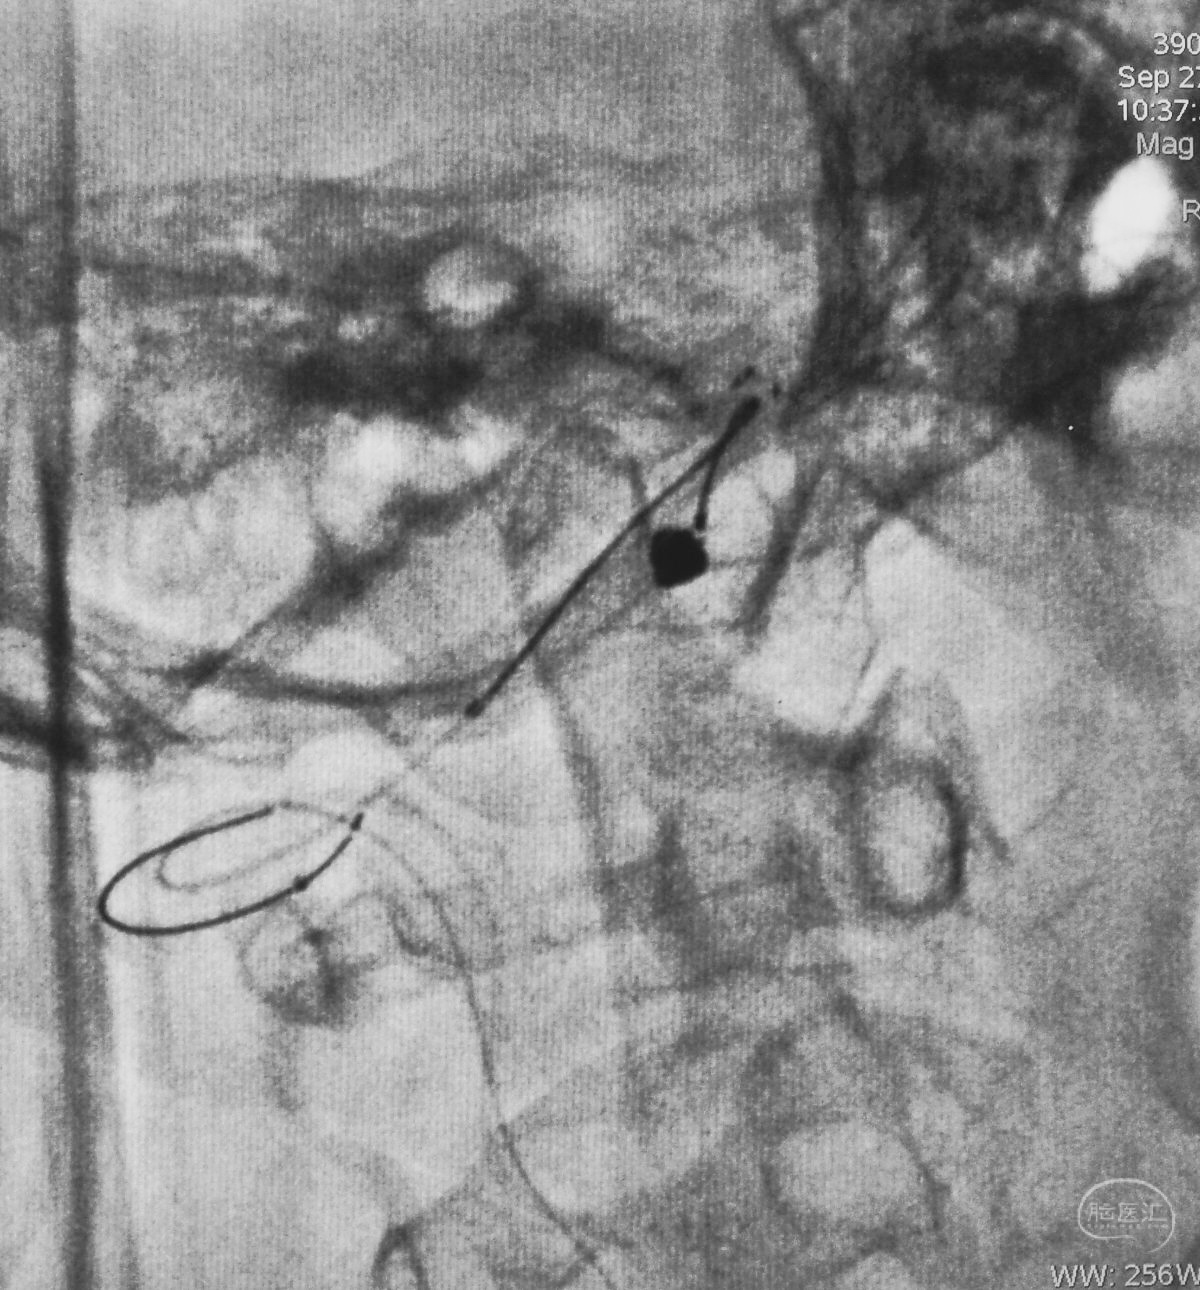

将微导管在虹吸弯处成襻,越过瘤颈,管头折返钩入瘤腔,即所谓回马枪技术。

Solitaire 4×15支架(绿线)跨瘤颈半释放,压住微导管(红线)。